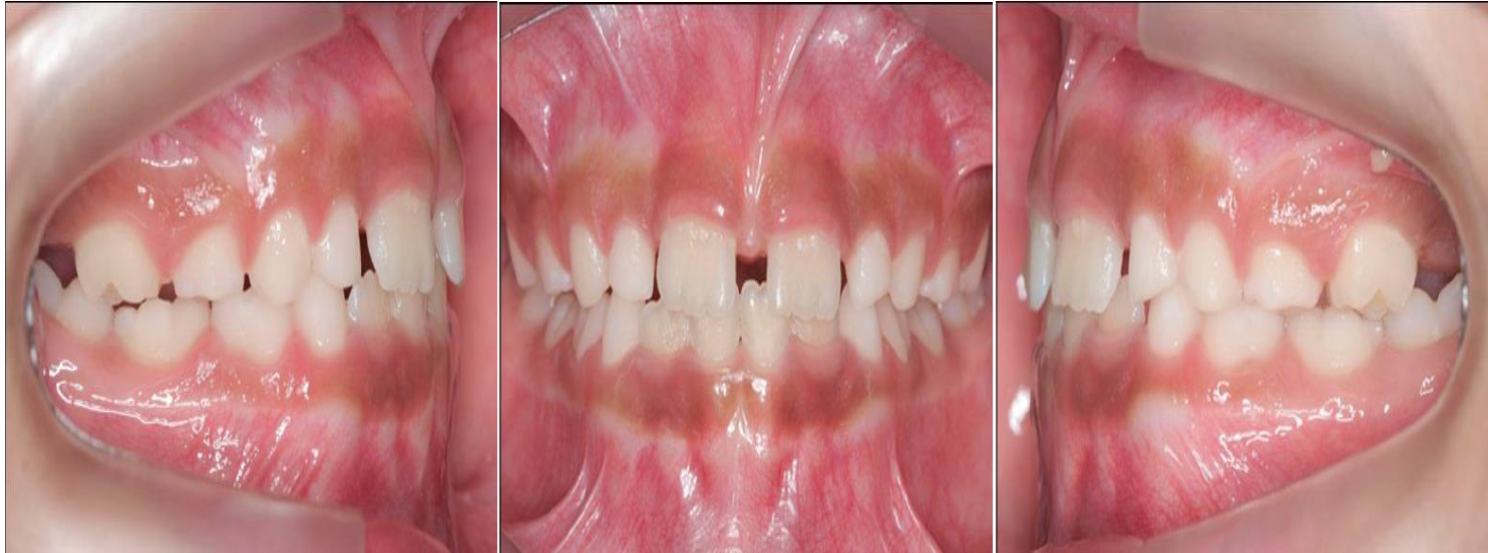

Después de realizar el examen clínico, anamnesis, y análisis del estudio de Ortodoncia, se escogieron 3 pacientes con edades entre 3 a 8 años, que presentaban las siguientes características: dentición decidua y mixta, perfil cóncavo, tipo morfológico mesofacial, deglutición y fonación normal, con buena higiene y respiración bucales, así como clase III esquelética con deficiencia maxilar y mordida cruzada anterior.

Autor: María Gabriela Flores Bracho. Fuente: Historia Clínica de M. C. M. H. 6 años. 04-2010.

Figura 1. Fotos de frente y perfil.

Autor: María Gabriela Flores Bracho. Fuente: Historia Clínica de M. C. M. H. 6 años. 04- 2010

Figura 2. Foto intrabucal. Vista frontal.

Figura 3. Fotos intrabucales. Vista lateral.

Figura 4. Fotos intrabucales. vista oclusal superior e inferior.